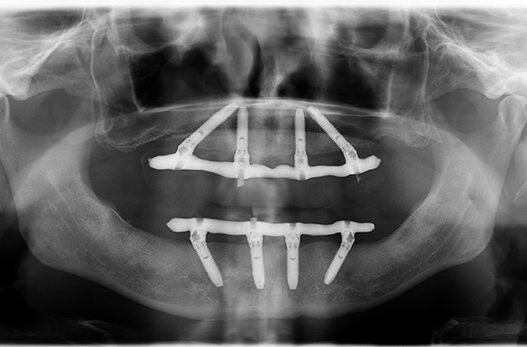

как выглядел протез "все на 4"

Как такая работа стала возможной? Пауло Мало предположил, что использование имплантов под углом позволяет обойти сложные участки, где очень мало костной ткани или она отсутствует.

Это позволяло успешно устанавливать импланты. Как раз для тех пациентов, у которых наблюдалась максимальная убыль кости, методика All-on-4 стала настоящим сюрпризом и подарком.